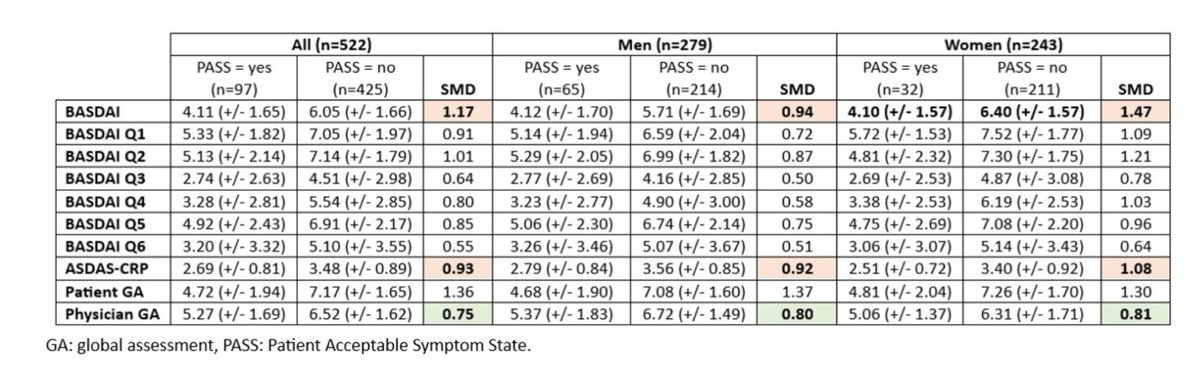

Gender based response in Axial SpA. A hot topic at ACR @ACRheum @RheumNow @hac28 @SPARTAN_Updates https://t.co/zbnE6kjQhL

Marina Magrey mmagrey1 ( View Tweet)

Gender differences in axSpA extend to dse activity assessment tools.

PREDICT-SpA:

🔶️BASDAI score performed better in women.

🔶️ ASDAS-CRP homogenous performance on both genders.

Consider BASDAI for assessing dse activity in women?

@RheumNow #ACR24 abs571

@rheumarhyme https://t.co/rKJXn2EPXa

sheila RHEUMarampa ( View Tweet)